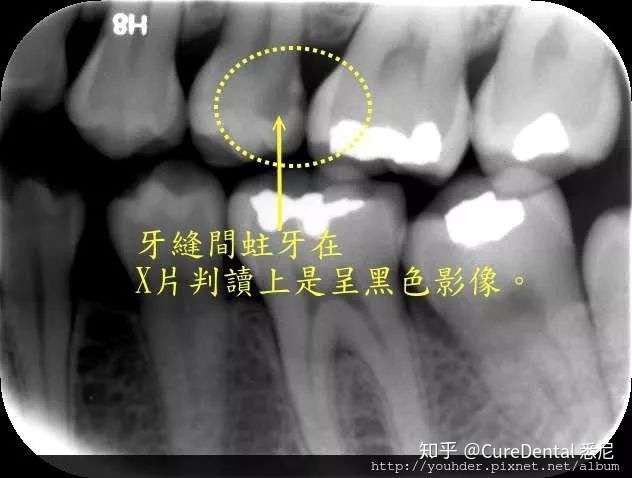

悉尼牙医爱拍x Ray 究竟是为什么 知乎

牙齿x光片怎么看蛀牙 万图壁纸网